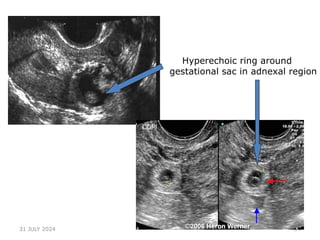

USG PICTURE

1.‘Bagel’ sign – Hyperechoic ring around gestational sac in adnexal

region

Hyperechoic ring around

gestational sac in adnexal region

Ring sign — a hyperechoic ring around an

extrauterine gestational sac.